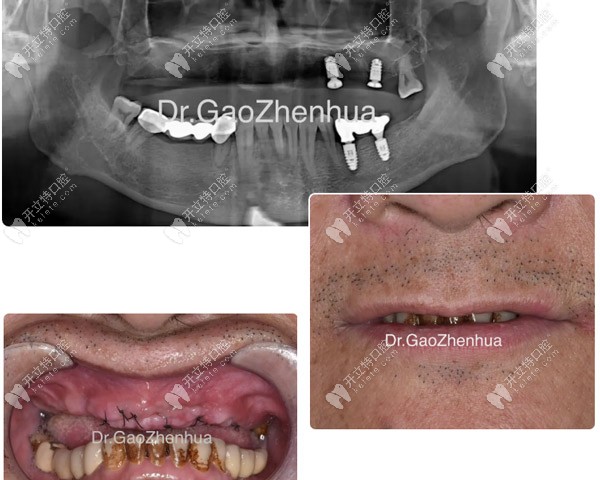

馮先生決定來鼎植治療缺骨問題,是因?yàn)?span style="color: rgb(255, 0, 0);">一年前做的6顆即刻負(fù)重短植體全部松動(dòng)脫落,在廣州各大口腔尋醫(yī)無效后才去的治療。

馮先生種植失敗后拍的CT片

馮先生種植失敗后拍的CT片▲

結(jié)果顯示:牙槽嵴多處缺骨、牙齒骨質(zhì)疏松,后牙區(qū)多位點(diǎn)缺骨并與竇腔貫連,好在結(jié)節(jié)翼板區(qū)骨量尚可。